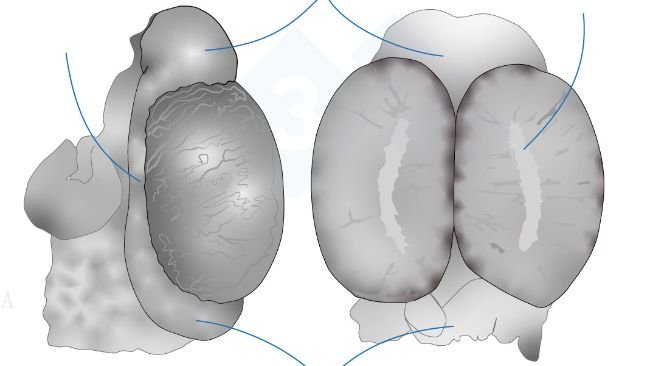

Este artigo revisa o efeito dos componentes da dieta sobre o osso e a osteocondrose, principal causa de claudicação e motivo da eliminação de reprodutores jovens. Portanto, conceitos importantes a serem considerados em dietas de criação de leitoas.